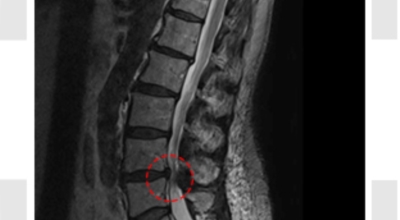

요추관 협착증은 척추 내 신경이 지나가는 통로가 좁아지는 현상으로 기인해서 신경이 눌리면서 이에 따른 여러가지 증상을 유발하는 질환을 의미해요.

허리 협착증은 척추관이 좁아지게 되면서 신경을 압박하게 되어 허리통증과 또한 다리에도 여러가지 증상을 일으키게 되는데, 발생 원인은 주로 노화로 인한 퇴행성 변화가 많았지만 요즈음는 옳지 않은 자세로 오랫동안 앉아있는 사람들이 많아지면서 생기는 경우도 많아졌으며, 선천적인 요인으로 나타나는 경우도 있답니다.

누운 자세로 두 다리를 모아 준후 안쪽으로 살짝만 굽혀서 다리 밑 공간이 삼각형을 이루도록 해 준 후, 허리를 바닥에 붙인 채로 골반만 30도 정도 기율여 줘요. 시계추가 움직이듯 왔다 갔다 하는 느낌으로 좌우 각각 10씩 5회 이상 해줍니다. 한사람 한사람의 체력에 맞게 해요.